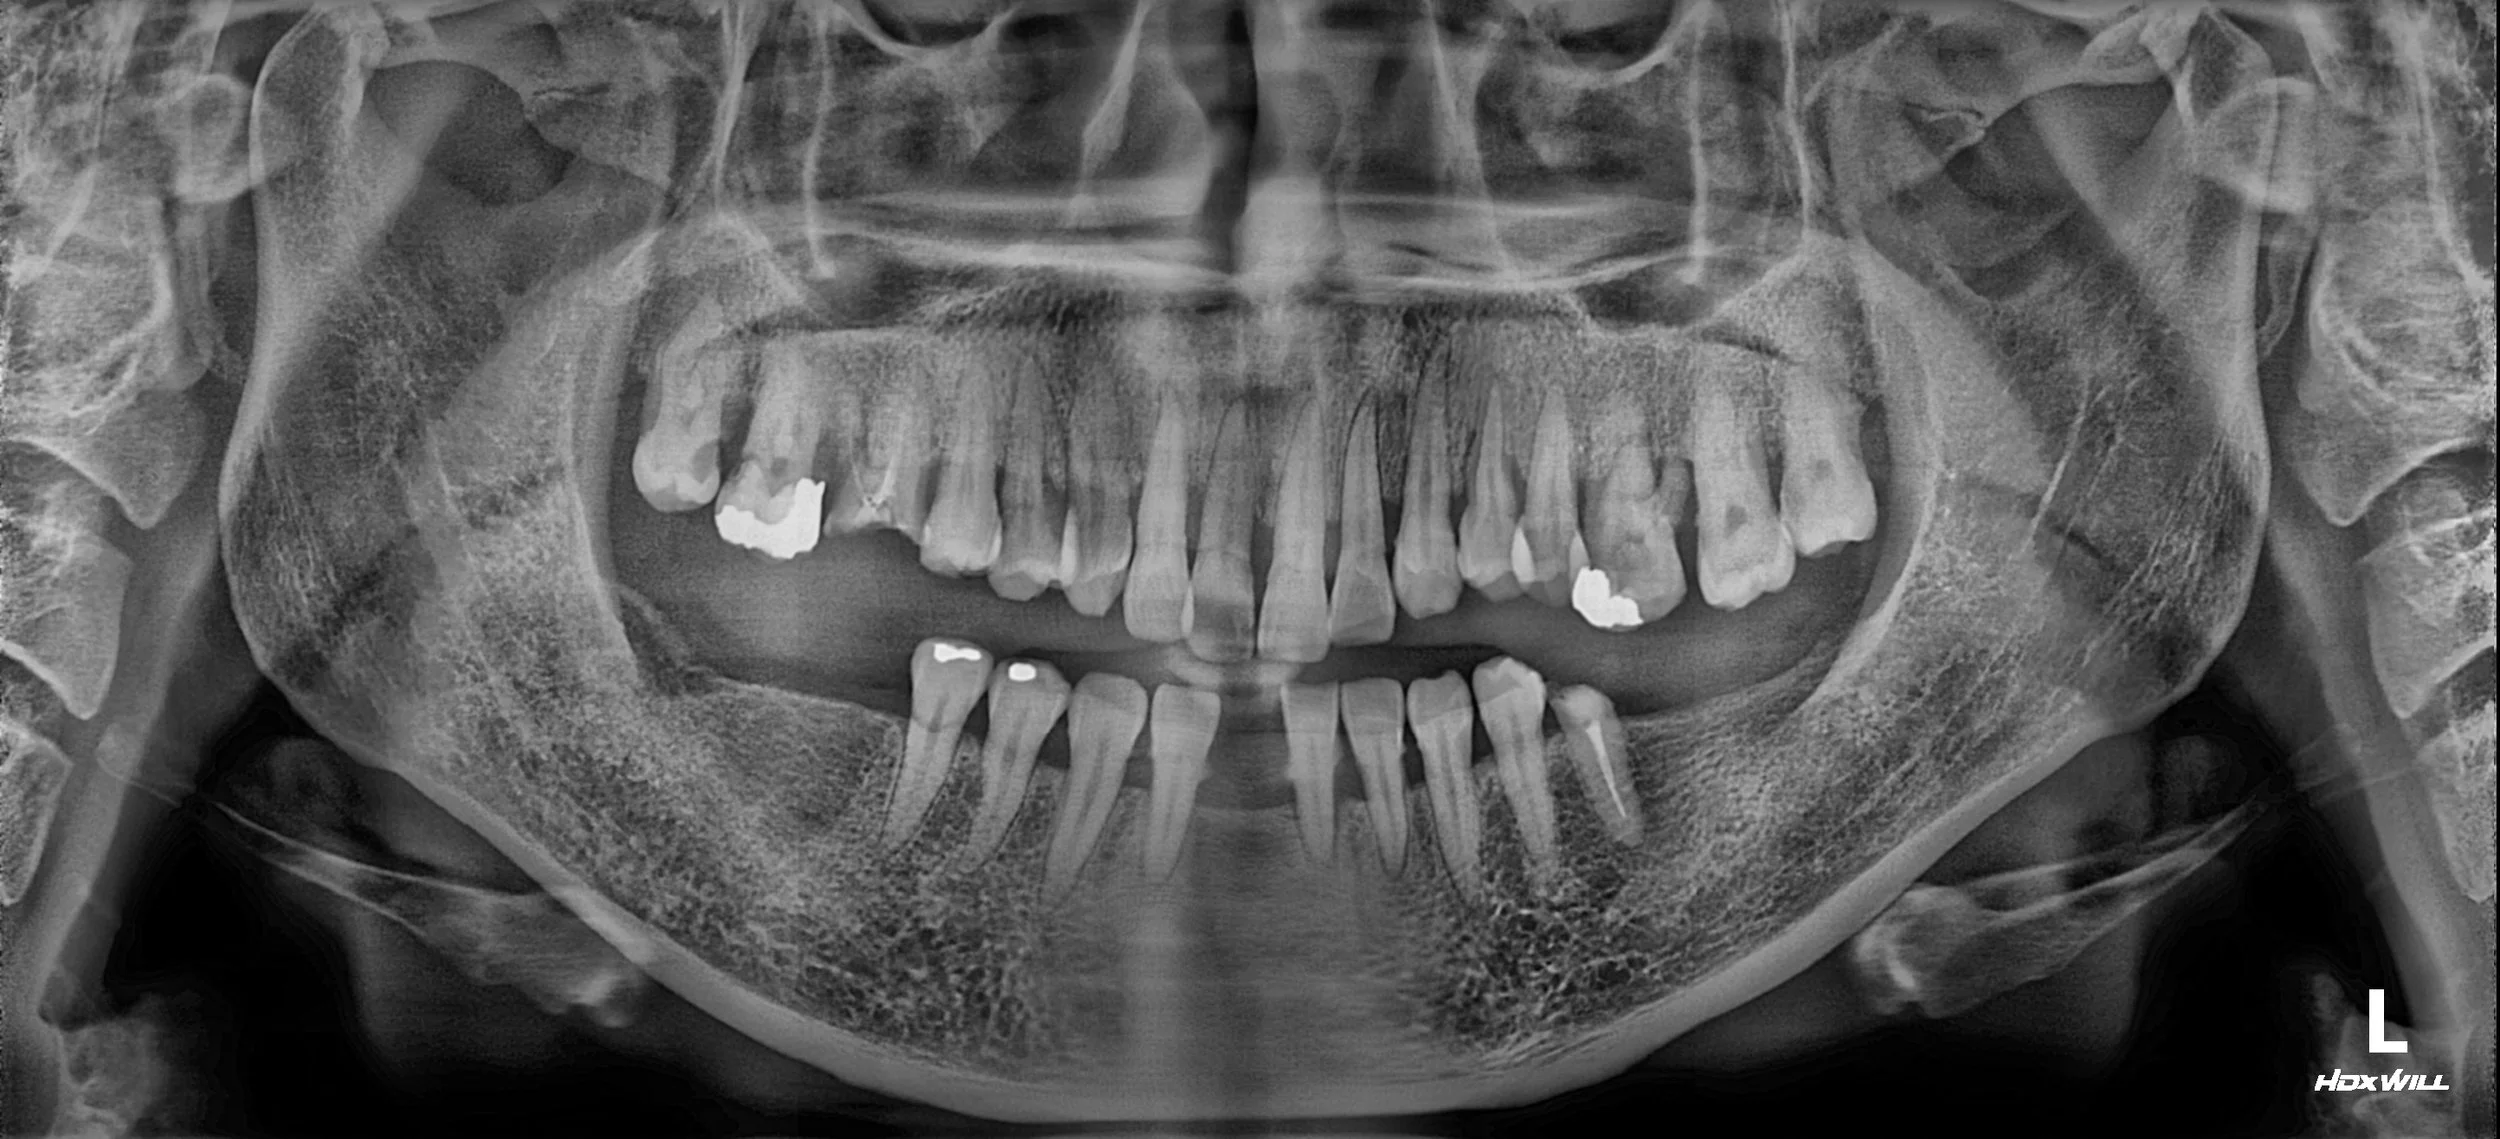

OPG - BEFORE

The patient presented with moderate to advanced periodontitis, posterior occlusal loss,

and partial anterior tooth loss accompanied by mobility of the remaining teeth.

Due to prolonged edentulism in the anterior region, the patient had largely abandoned

esthetic expectations and adapted to a compromised functional state.